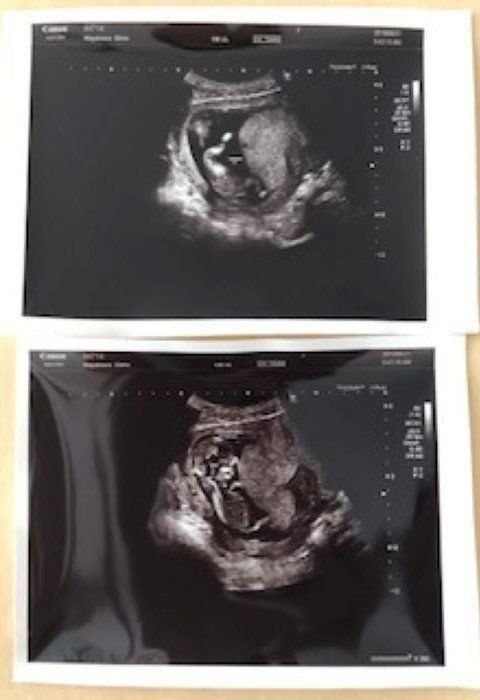

第24週 エコー写真に目線がピッタリ

24w2d

妊娠24週目の健診時、赤ちゃんがバッチリとこちらに向いている時のエコー写真です。エコー検査で見た赤ちゃんは、顔を左右に動かしたり、手足をバタバタと器用に動かしたりと、子宮内の環境にすっかり馴染んでいるように私には見えました。左の写真はパンチをした瞬間です。エコー検査の間も何回か胎動を感じていました。